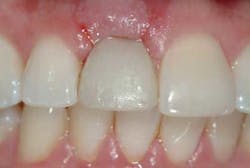

Of all the problems that can occur with implant placement in the anterior, not controlling the zenith of gingival contour may be the most troublesome when it comes to anterior esthetics. Gingival zenith or height of gingival contour is defined as the apex of the gingival height. There are many ways to lose several millimeters of peri-implant mucosa, and it has been shown that even a 1 mm apical displacement of peri-implant mucosa may result in insurmountable limitations in anterior implant esthetics. Things such as deep implant placement, buccal resorption, and relative tooth eruption are just some of the things that can cause this loss of tissue.

Now comes the tricky part — the provisional. Prosthetic control of peri-implant tissue is achieved by properly utilizing your abutment and provisional form. When placing the provisional, it is important to maintain gingival zenith. When fabricating a provisional, my rule of thumb is to create a flat or slightly convex surface facially and lingually, and a concave surface interproximally. This will minimize impingement on the tissue interproximally and, if anything, allow for “overgrown tissue” to develop. This tissue can be easily contoured prior to final placement to give an ideal esthetic gingival architecture.

Usain Bolt trained for years to prepare for a 10-second Olympic race, a race that made him a world superstar. He didn’t walk up to the track the day of the Olympics and blow away the competition. He spent countless hours preparing physically and mentally for that one moment in the spotlight. The same dedication applies to dentistry. When an anterior implant case is planned properly among the surgeon, dentist, and ceramist, the result can be as rewarding as Olympic gold.Before